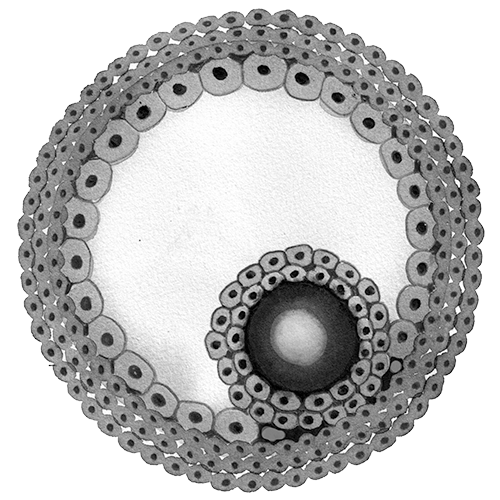

How an egg retrieval works

Around that time, researchers began experimenting with freezing eggs. Success rates were low. The human egg is 90% water, and when it freezes, ice crystals can damage the delicate spindle of chromosomes inside. Even as IVF became mainstream, only a few births using frozen eggs occurred over the next two decades.

By the early 2000s a new technology, known as vitrification, allowed eggs to be frozen so quickly that the fluid has no time to form crystals and instead turns into a glasslike solid. In 2012 two of the world’s largest organizations representing fertility practitioners backed the technique. Vitrification boomed. In the US alone, the number of fertility procedures using frozen donor eggs or embryos tripled from 2012 to 2021, to 26,700, according to the Centers for Disease Control and Prevention.